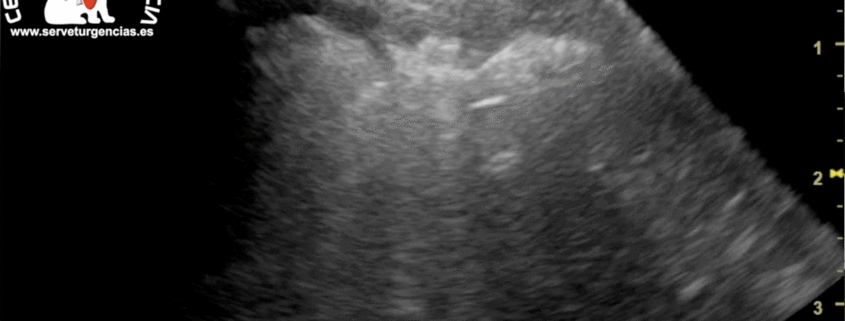

El aumento de líquido en el saco pericárdico produce un aumento de presión que lleva al colapso